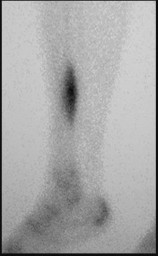

Differentiating Charcot from osteomyelitis is difficult because both show hyperperfusion and bony changes. A combined Indium-111 WBC scan and Tc-99m sulfur colloid bone marrow scan is highly specific. In Charcot arthropathy, there is increased bone turnover and marrow expansion, leading to matched uptake on both scans. In osteomyelitis, the infection suppresses the normal marrow, leading to mismatched uptake (increased WBC uptake, decreased marrow uptake).